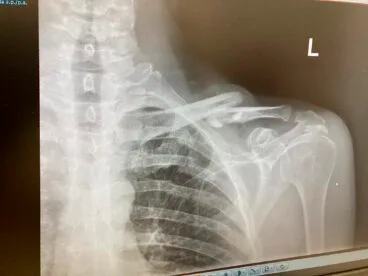

28 de enero de 2024 - 09:37 Foto Anterior3 de 5Foto SiguienteVer el artículo original: Cuando un mal golpe con los jabalíes te manda al hospital: ¿es posible combatir la plaga en la Marina Alta? Ramón Mut tras recibir el alta del hospital Radiografía de la clavícula rota del ciclista Ramón Mut, ciclista de Ondara en el hospital después del accidente con los jabalíes Ramón Mut, ciclista de Ondara en el hospital después del accidente con un jabalí Jabalíes dentro de Xàbia